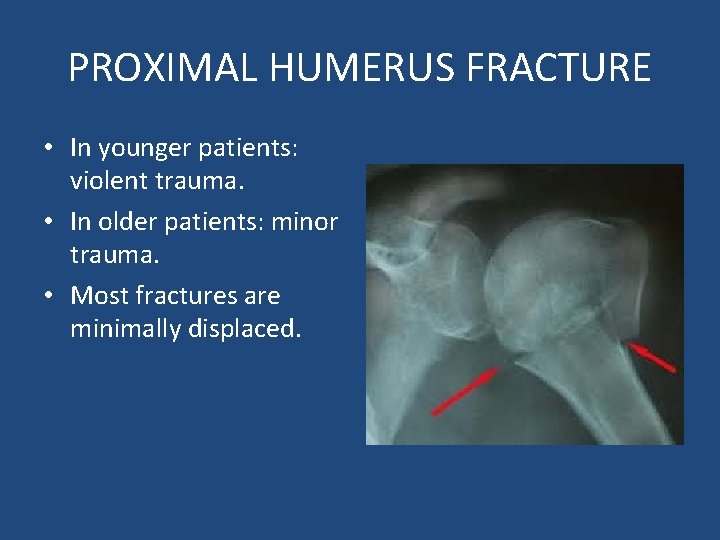

PROXIMAL HUMERUS FRACTURE • In younger patients: violent trauma. • In older patients: minor trauma. • Most fractures are minimally displaced.

X-rays • Fracture is defined by the fragments displaced. • Displacement: more than 1 cm.